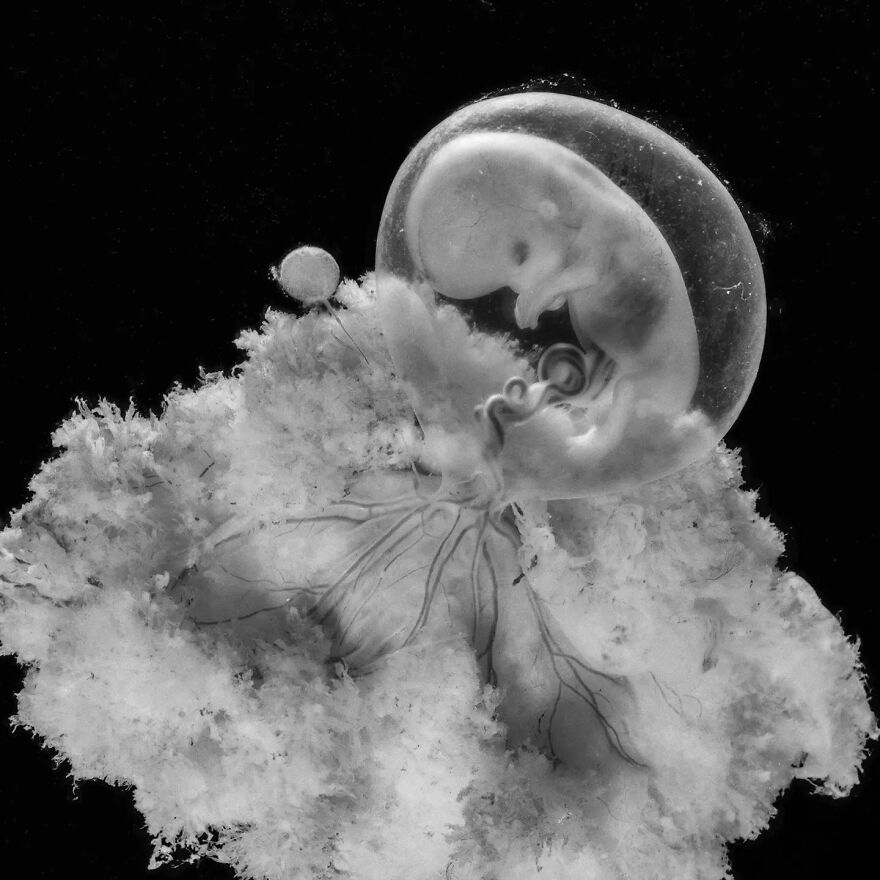

Работы знаменитого фотографа Леннарта Нильссона

Раздел: Фотопанорама